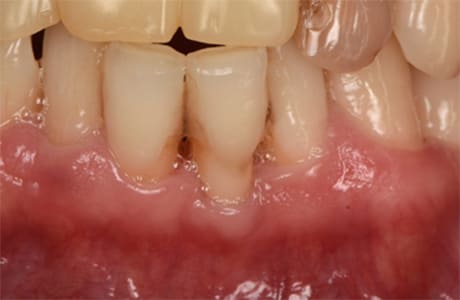

初診時の口腔内

「前歯の歯ぐきの腫れが引かない」と来院された20代女性の患者さまです。

数年前に他院でセラミック治療を受けた後から、歯ぐきの腫れが続いており、なかなか改善しないことを気にされていました。

初診時の口腔内写真からもわかるように、特に前歯の歯肉が赤く腫れ上がっている状態でした。